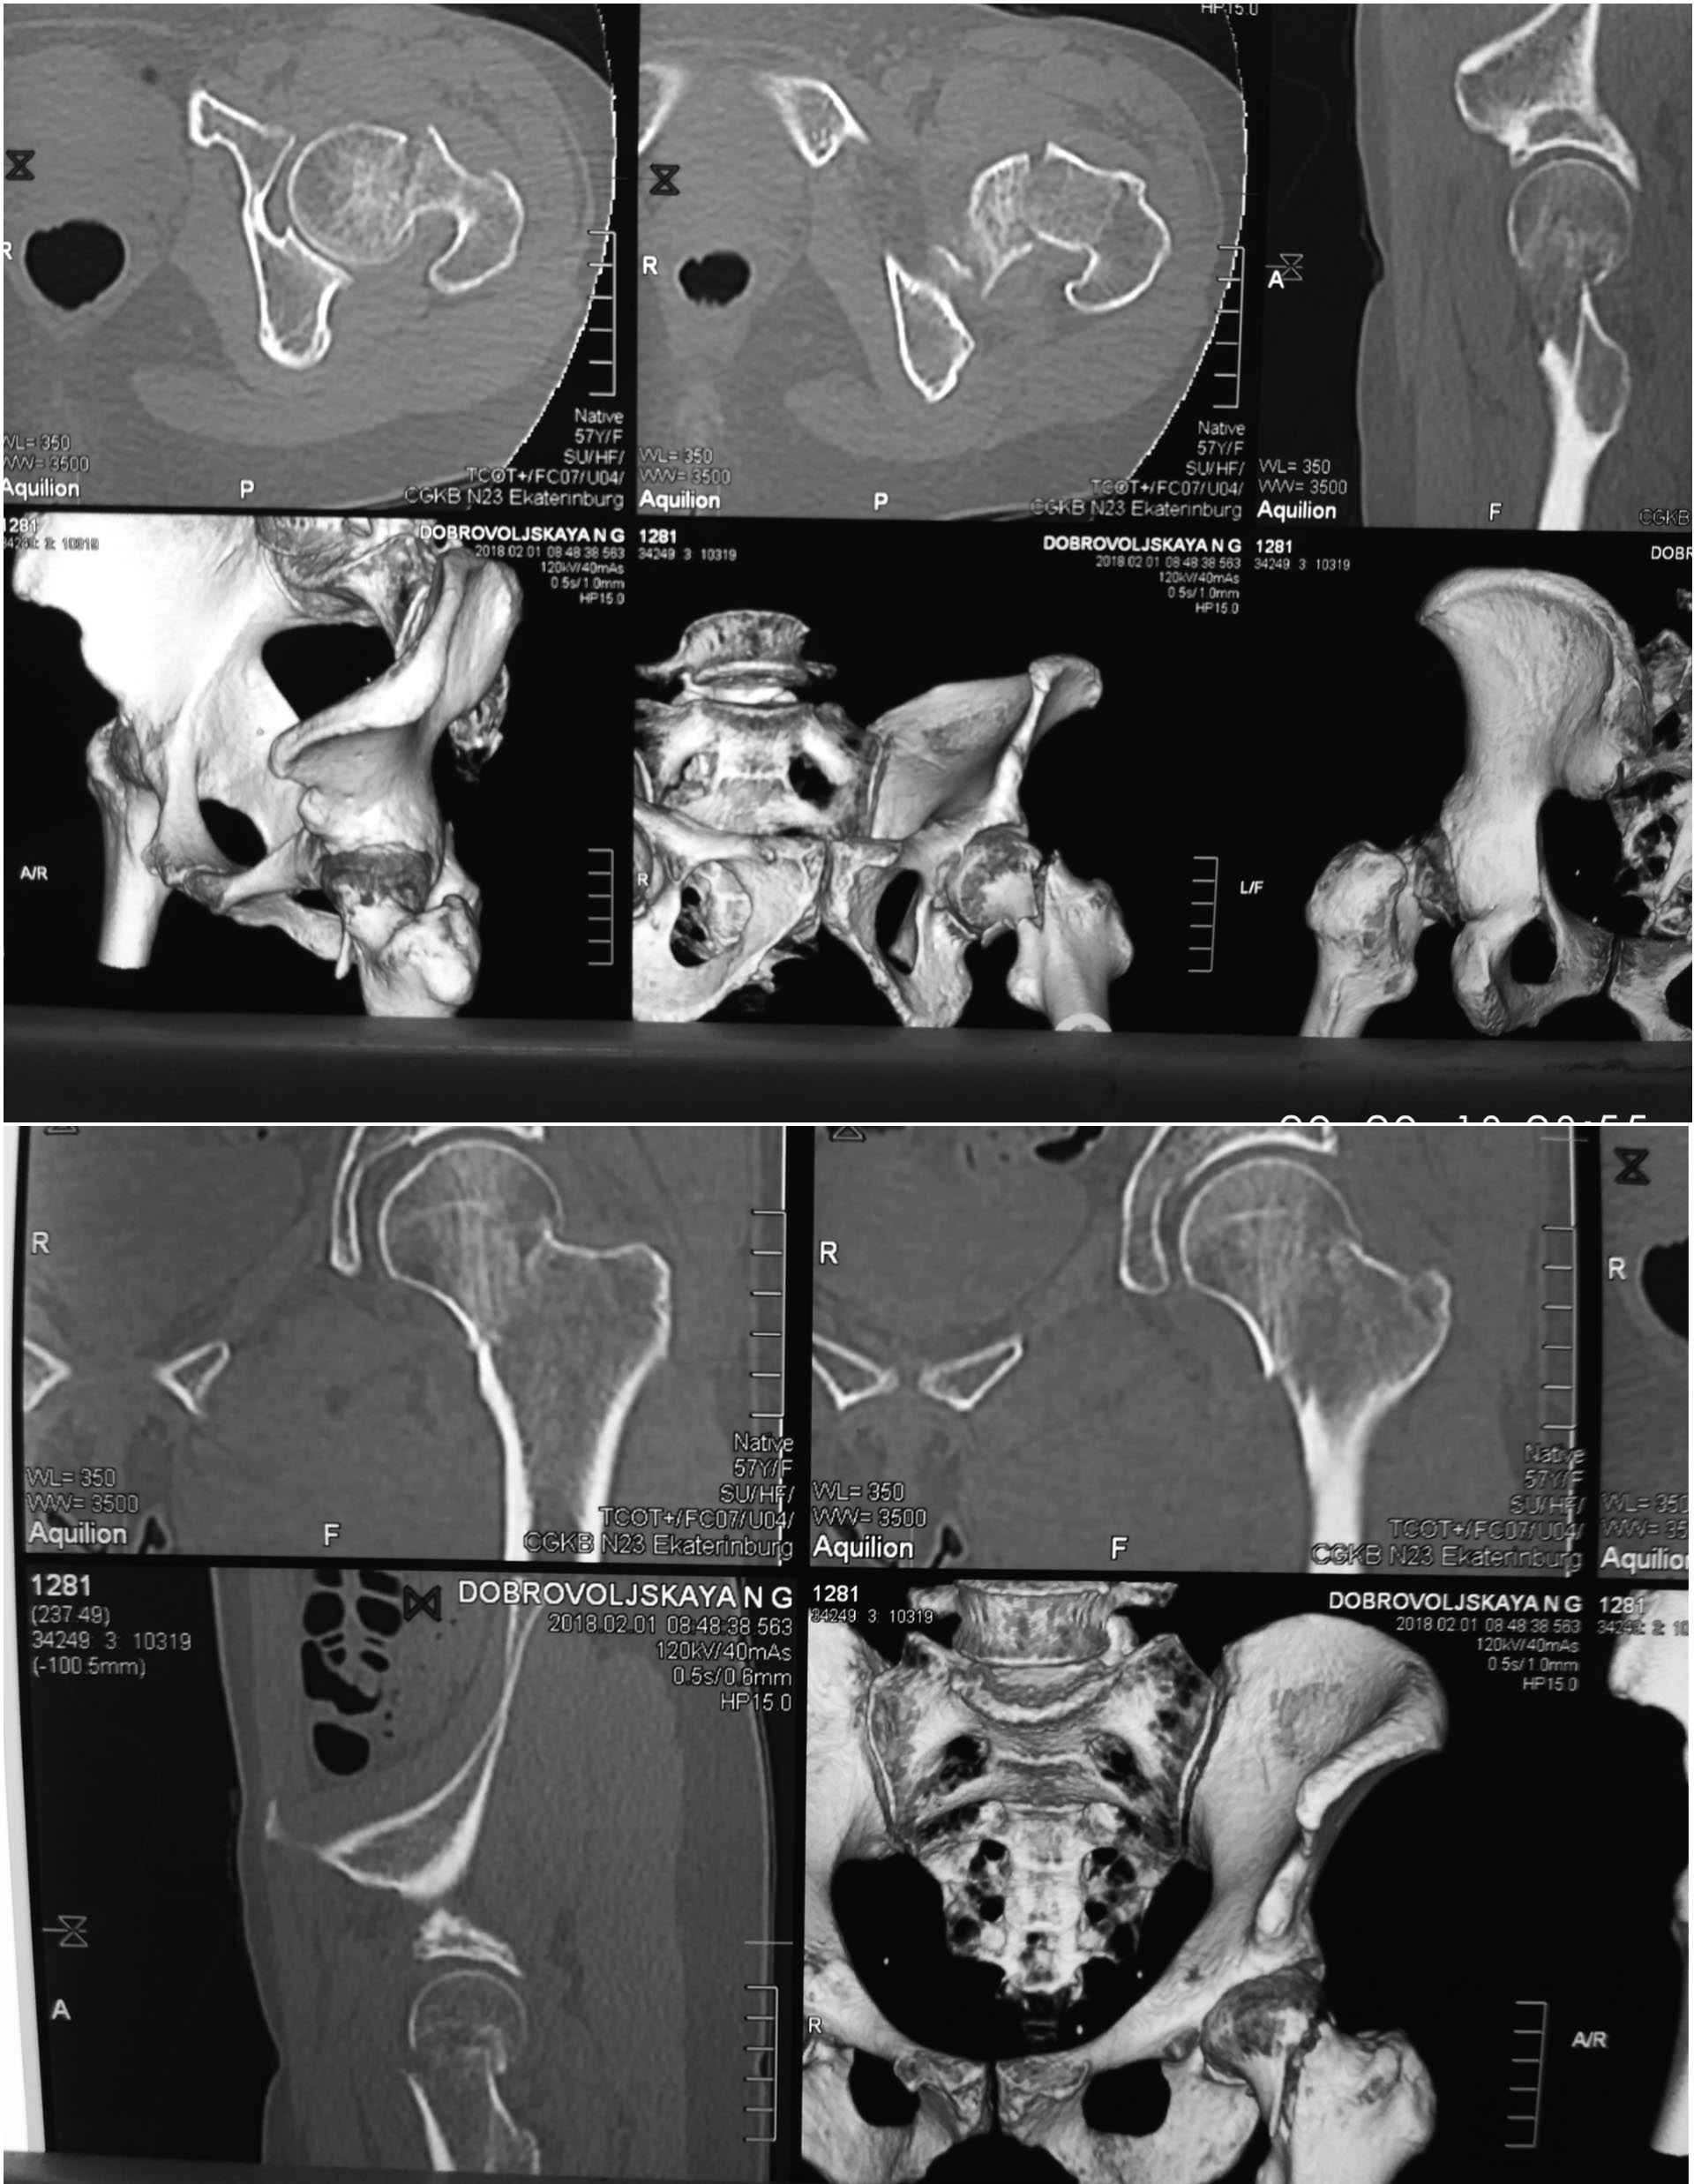

Помогите в выборе тактике и импланта

Пациентка ,57 лет ,сохранна ,активная. Травма низкой энергии. Помогите

решить два вопроса - эндопротезирование или синтез? Если синтез,то чем?

(какой имплант , репозиоционные маневры ,открыто или закрыто)